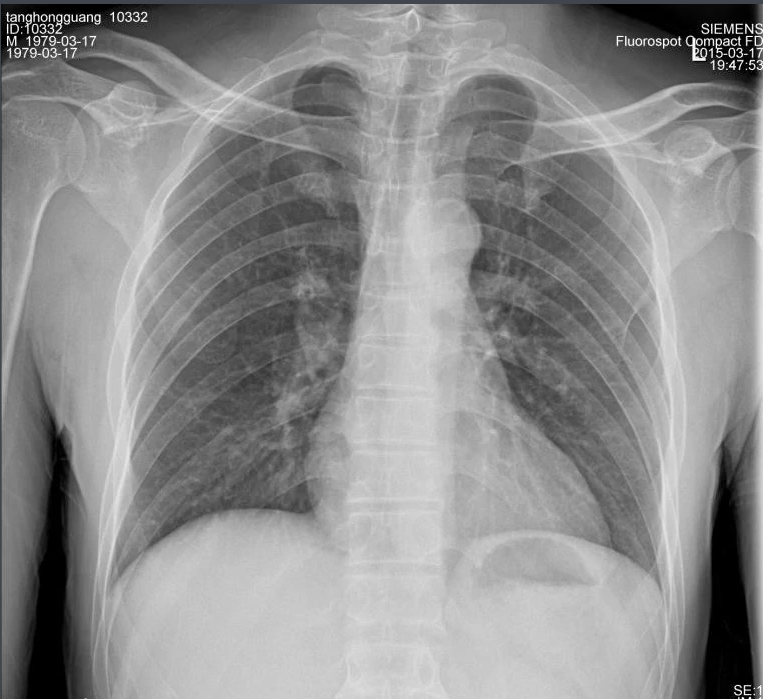

X射线,是一种频率极高,波长极短、能量很大的电磁波。具有穿透性,但人体组织间有密度和厚度的差异,当X射线透过人体不同组织时,被吸收的程度不同,经过显像处理后即可得到不同的影像。下面那我们来聊一聊关于X射线的三大特性分别是哪些。

X射线因其波长短,能量大,照在物质上时,仅一部分被物质所吸收,大部分经由原子间隙而透过,表现出很强的穿透能力。X射线穿透物质的能力与X射线光子的能量有关,X射线的波长越短,光子的能量越大,穿透力越强。X射线的穿透力也与物质密度有关,利用差别吸收这种性质可以把密度不同的物质区分开来 。

X射线同可见光一样能使胶片感光。胶片感光的强弱与X射线量成正比,当X射线通过人体时,因人体各组织的密度不同,对X射线量的吸收不同,胶片上所获得的感光度不同,从而获得X射线的影像  。